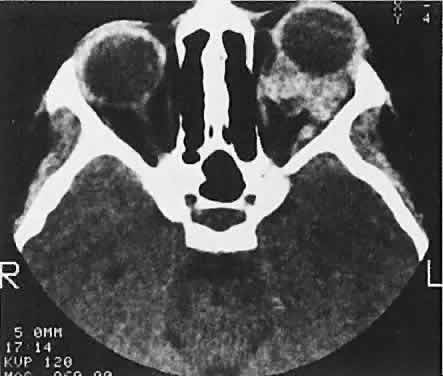

In dacryoadenitis, external inflammatory signs are localized to the superotemporal quadrant, and CT shows enlargement of the lacrimal gland (Fig. 24). Lacrimal gland inflammation may be bacterial, viral, or a variant of IIPT. It is possible, however, that many cases of “idiopathic” dacryoadenitis represent unidentified viral infections. In bacterial dacryoadenitis, a leukocytosis with a left shift may be present.96 In questionable cases, a 1-week course of oral antibiotics can be administered to these patients. Among children, the probability that an enlarged lacrimal gland represents neoplasia rather than inflammation is lower than among adults, although epithelial lacrimal gland tumors occasionally may occur in the pediatric population and can produce external inflammatory signs. If the general signs and symptoms of IIPT are lacking, a biopsy should be performed. Histopathologically, IIPT is characterized by a sparse, mixed inflammatory cell infiltration of the tissues primarily involved (i.e., extraocular muscle, lacrimal gland, Tenon's fascia). The predominant cell is a mature lymphocyte, but there are significant numbers of polymorphonuclear neutrophils, plasma cells, and eosinophils.95 As the inflammatory process evolves, fibrosis becomes a prominent feature. In the variant of IIPT termed sclerosing pseudotumor, collagen deposition is an early finding, and the fibroblast may be the primary mediator of the inflammatory process rather than the lymphocyte.97,98 If the histopathologic findings include true vasculitis (i.e., destruction of vessel wall intima and muscularis) or granulomatous inflammation (i.e., epithelioid and giant cells), Wegener's granulomatosis and other systemic diseases should be excluded. By definition, if a systemic process is confirmed, the IIPT designation no longer applies. If the microscopic picture is dominated by a highly cellular population of uniform lymphocytes, the spectrum of reactive and neoplastic lymphoid lesions should be suspected rather than IIPT. IIPT usually shows a dramatic response to high doses of oral corticosteroids. Clinical improvement occurs within several days, but treatment should be tapered slowly to prevent recrudescence of the inflammation. A pediatrician should collaborate in the treatment of young children with corticosteroids because of the risks of growth retardation and other complications. Although the etiology remains unknown, this exquisite treatment response adds credence to an immunologic basis. Patients tend to follow one of three long-term clinical patterns: single unilateral episodes; recurrent unilateral episodes; or recurrent bilateral episodes, usually alternating from one orbit to the other.94 Among children with IIPT, bilateral involvement and an anterior uveal component prognosticate a more severe course in terms of multiple recurrences and permanent vision loss. Sclerosing pseudotumor, which may involve a distinctly different pathogenesis, generally carries a poorer prognosis with a higher likelihood of cicatricial entrapment of orbital structures.97 Early aggressive treatment with corticosteroids is indicated.Surgical debulking may be necessary, and immunosuppressive agents may be needed in refractory cases. ORBITAL CELLULITIS Orbital cellulitis and its variants are the most common causes of rapidly progressive proptosis in childhood. The term orbital cellulitis often is applied broadly to an anatomic spectrum of bacterial infection, including preseptal cellulitis, diffuse orbital cellulitis, subperiosteal abscess (SPA), intraorbital abscess and, in rare complicated or neglected cases, cavernous sinus thrombosis. In children, possible etiologies include penetrating trauma, extension of local periocular infection (e.g., impetigo or dacryocystitis), and hematogenous seeding from a distant site (e.g., otitis media).99 However, orbital cellulitis most often results from bacterial infection of the paranasal sinuses, which share insubstantial bony walls and an extensive valveless venous system with the orbits.59,100 The clinical profile includes eyelid edema and erythema. If there is true orbital involvement, there may be proptosis, chemosis, and diminished motility. Diagnosis is aided by a history of antecedent respiratory tract infection and signs of systemic toxicity, including fever and leukocytosis. The CT findings of sinus opacification and an orbital abnormality suggest the diagnosis. However, rhabdomyosarcomas and neuroblastomas may affect the orbits and sinuses simultaneously. In these cases, destructive bone change might be expected. The initial recognition of orbital infection generally is not problematic. However, appropriate management requires other early determinations, including proper staging and risk assessment. If CT scans show only preseptal or orbital cellulitis, the prompt administration of appropriate intravenous antibiotics to these well-perfused tissues should be curative. If, however, infection is sequestered in the relatively avascular subperiosteal space (Fig. 25), concerns are raised about achieving therapeutic drug levels.59 An SPA also may have visual implications. The rapid accumulation and extension of purulent material within this potential space can increase orbital pressure, compromising optic nerve or retinal perfusion. There also are well-documented age-related variations in both the bacteriology and clinical response of the SPA/sinusitis complex.101,102 Children younger than 9 years of age are more likely to improve without surgical drainage of the sinuses or orbit, to have negative cultures if drained, or to have cultures positive for single aer-obes if drained within the first 3 days of treatment. Patients 15 years of age or older are more likely to have refractory infections, with positive cultures after more than 3 days of antibiotics usually effective in vitro, and to harbor multiple pathogens, including mixed aerobes and anaerobes. The 9- to 14-year-old age group shows a transition from simple to complex infections. Management includes otolaryngology consultation: nasal decongestion promotes nonsurgical sinus drainage; if surgery is needed, the orbit and sinuses should be drained simultaneously. Antibiotics are given intravenously. At present, appropriate choices include ampicillin/sulbactam for all age groups or a third-generation cephalosporin for children younger than 9 years of age, with the addition of clindamycin for patients 9 years of age or older. Because the inventory of available drugs is continually changing, consultation with infectious disease specialists may be appropriate. Surgical drainage of an SPA and the responsible sinuses is performed as soon as possible if optic nerve or retinal function is impaired by the mass effect (any age). Surgical drainage within 24 hours of presentation is recommended for large SPAs causing pain, for those along the superior or inferior orbital walls, for patients with frontal sinusitis, and in cases in which anaerobic pathogens are suspected (e.g., infections of known dental origin, chronic sinusitis, patients 9 years of age or older). In the absence of these surgical criteria, expectant observation, with inpatient antibiotic administration, is elected for children younger than 9 years of age with small- to moderate-sized medial SPAs.101,102 This approach requirescareful monitoring, and conservatively treated patients still default to surgery if a prompt clinical response is not noted. This judgment should not be made on the basis of serial CT scans alone, since SPAs may enlarge during the first few days of antibiotic therapy that ultimately proves effective.101,103 Garcia and Harris104 prospectively applied this protocol to a cohort of 37 patients younger than 9 years of age. Eight children met criteria for surgical treatment and underwent prompt drainage. Of the 29 patients for whom initial nonsurgical treatment was recommended, 27 (93%) recovered with antibiotics alone, and two defaulted to surgery. All patients had successful clinical outcomes. |